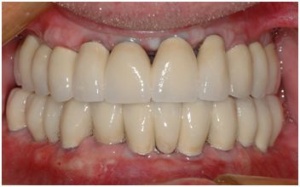

-la réalisation des bridges céramique définitifs.